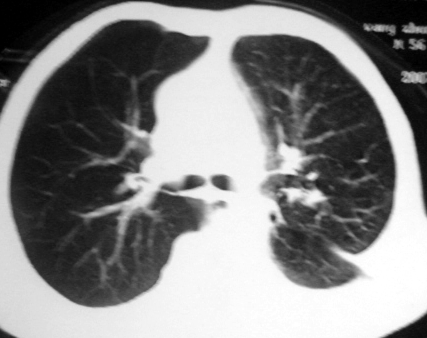

男,54岁,咳嗽,气喘半年,胸痛一月.

血性胸水

左侧胸腔积液 斜裂积液 心包积液 左肺不张 考虑左肺ca并胸膜心包转移。

支持左肺下叶中心型肺癌(累及舌叶)伴阻塞性肺炎、膨胀不全、胸腔积液、心包少量积液。

考虑左肺下叶中央型肺癌伴阻塞性肺炎及肺不张,纵隔受累可能,胸膜转移。